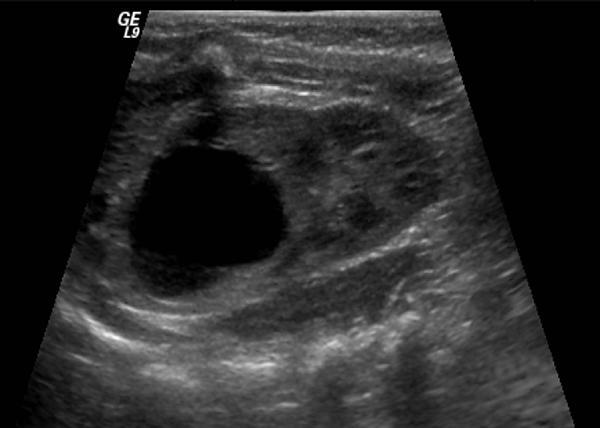

A one-month-old boy has a history of unilateral prenatal hydroureteronephrosis. An ultrasound of the right kidney is shown. The most likely explanation for the finding is:

3

The ultrasound demonstrates a duplicated system with upper pole hydronephrosis. The most likely explanation for this finding in a newborn is an ectopic upper pole ureter. The upper pole of a duplex system has a higher incidence of ectopia than the lower pole ureter because the upper pole ureter originates higher on the mesonephric duct and requires absorption of a longer segment of common excretory duct before it becomes incorporated in the bladder. The hydronephrosis results from distal ureteral obstruction as the ureter passes through the sphincteric mechanism of the bladder neck. UPJ obstruction of the upper pole segment is possible but much less common and would not have a dilated ureter. VUR into the upper pole is possible in association with ectopia, although VUR is usually not present with an ectopic upper pole ureter. A renal cyst or a calyceal diverticulum would be contained within surrounding normal renal tissue.